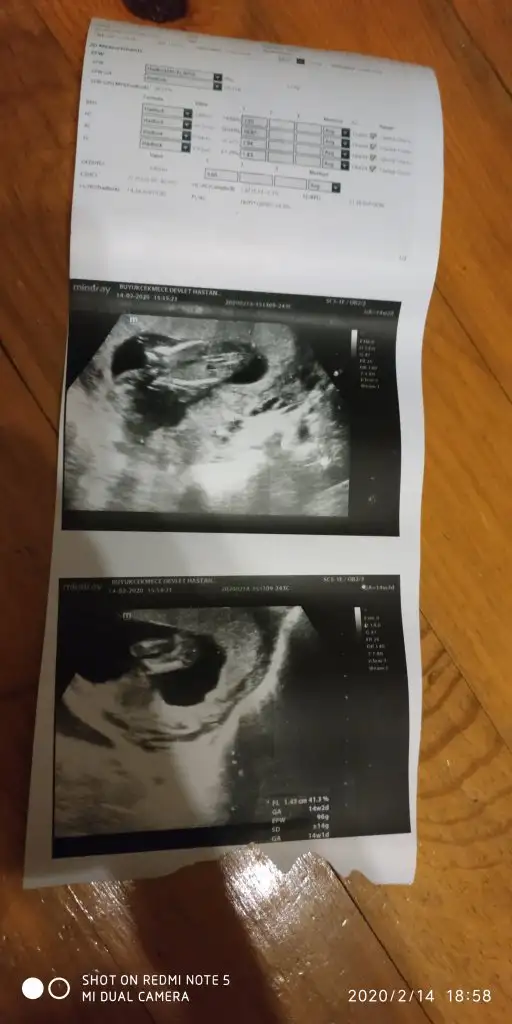

Tam net değil usg dr çıktısı yokmu bu usglerde emin olamadım sanki diyerek kız gibi gibi tekrar usg bekliyorum

Var tabiki ama ne olmadığı için ekran fotoğrafı yolladım

Canım 14+2 doktorum kıza benzetti dedim ben tereddutteyım daha önce erkeğe benzetildi ikili yltarama testinde İkra meyra

Dr. umda çok düşük ihtimal ile kız olabilir diye tahmin etti. Ama netlik için çok çok erken 2 hafta sonra netleşir dedi.

Canım ben 11+ yada 12 + nublara bakıyorum 14+2 de nub degil organı gelişmiş oluyor hadi 13 de olabilir usg dr kız dediyse kızdır cnm hmm 12 de erkek dedi diyorsun. hayırlısı olsun